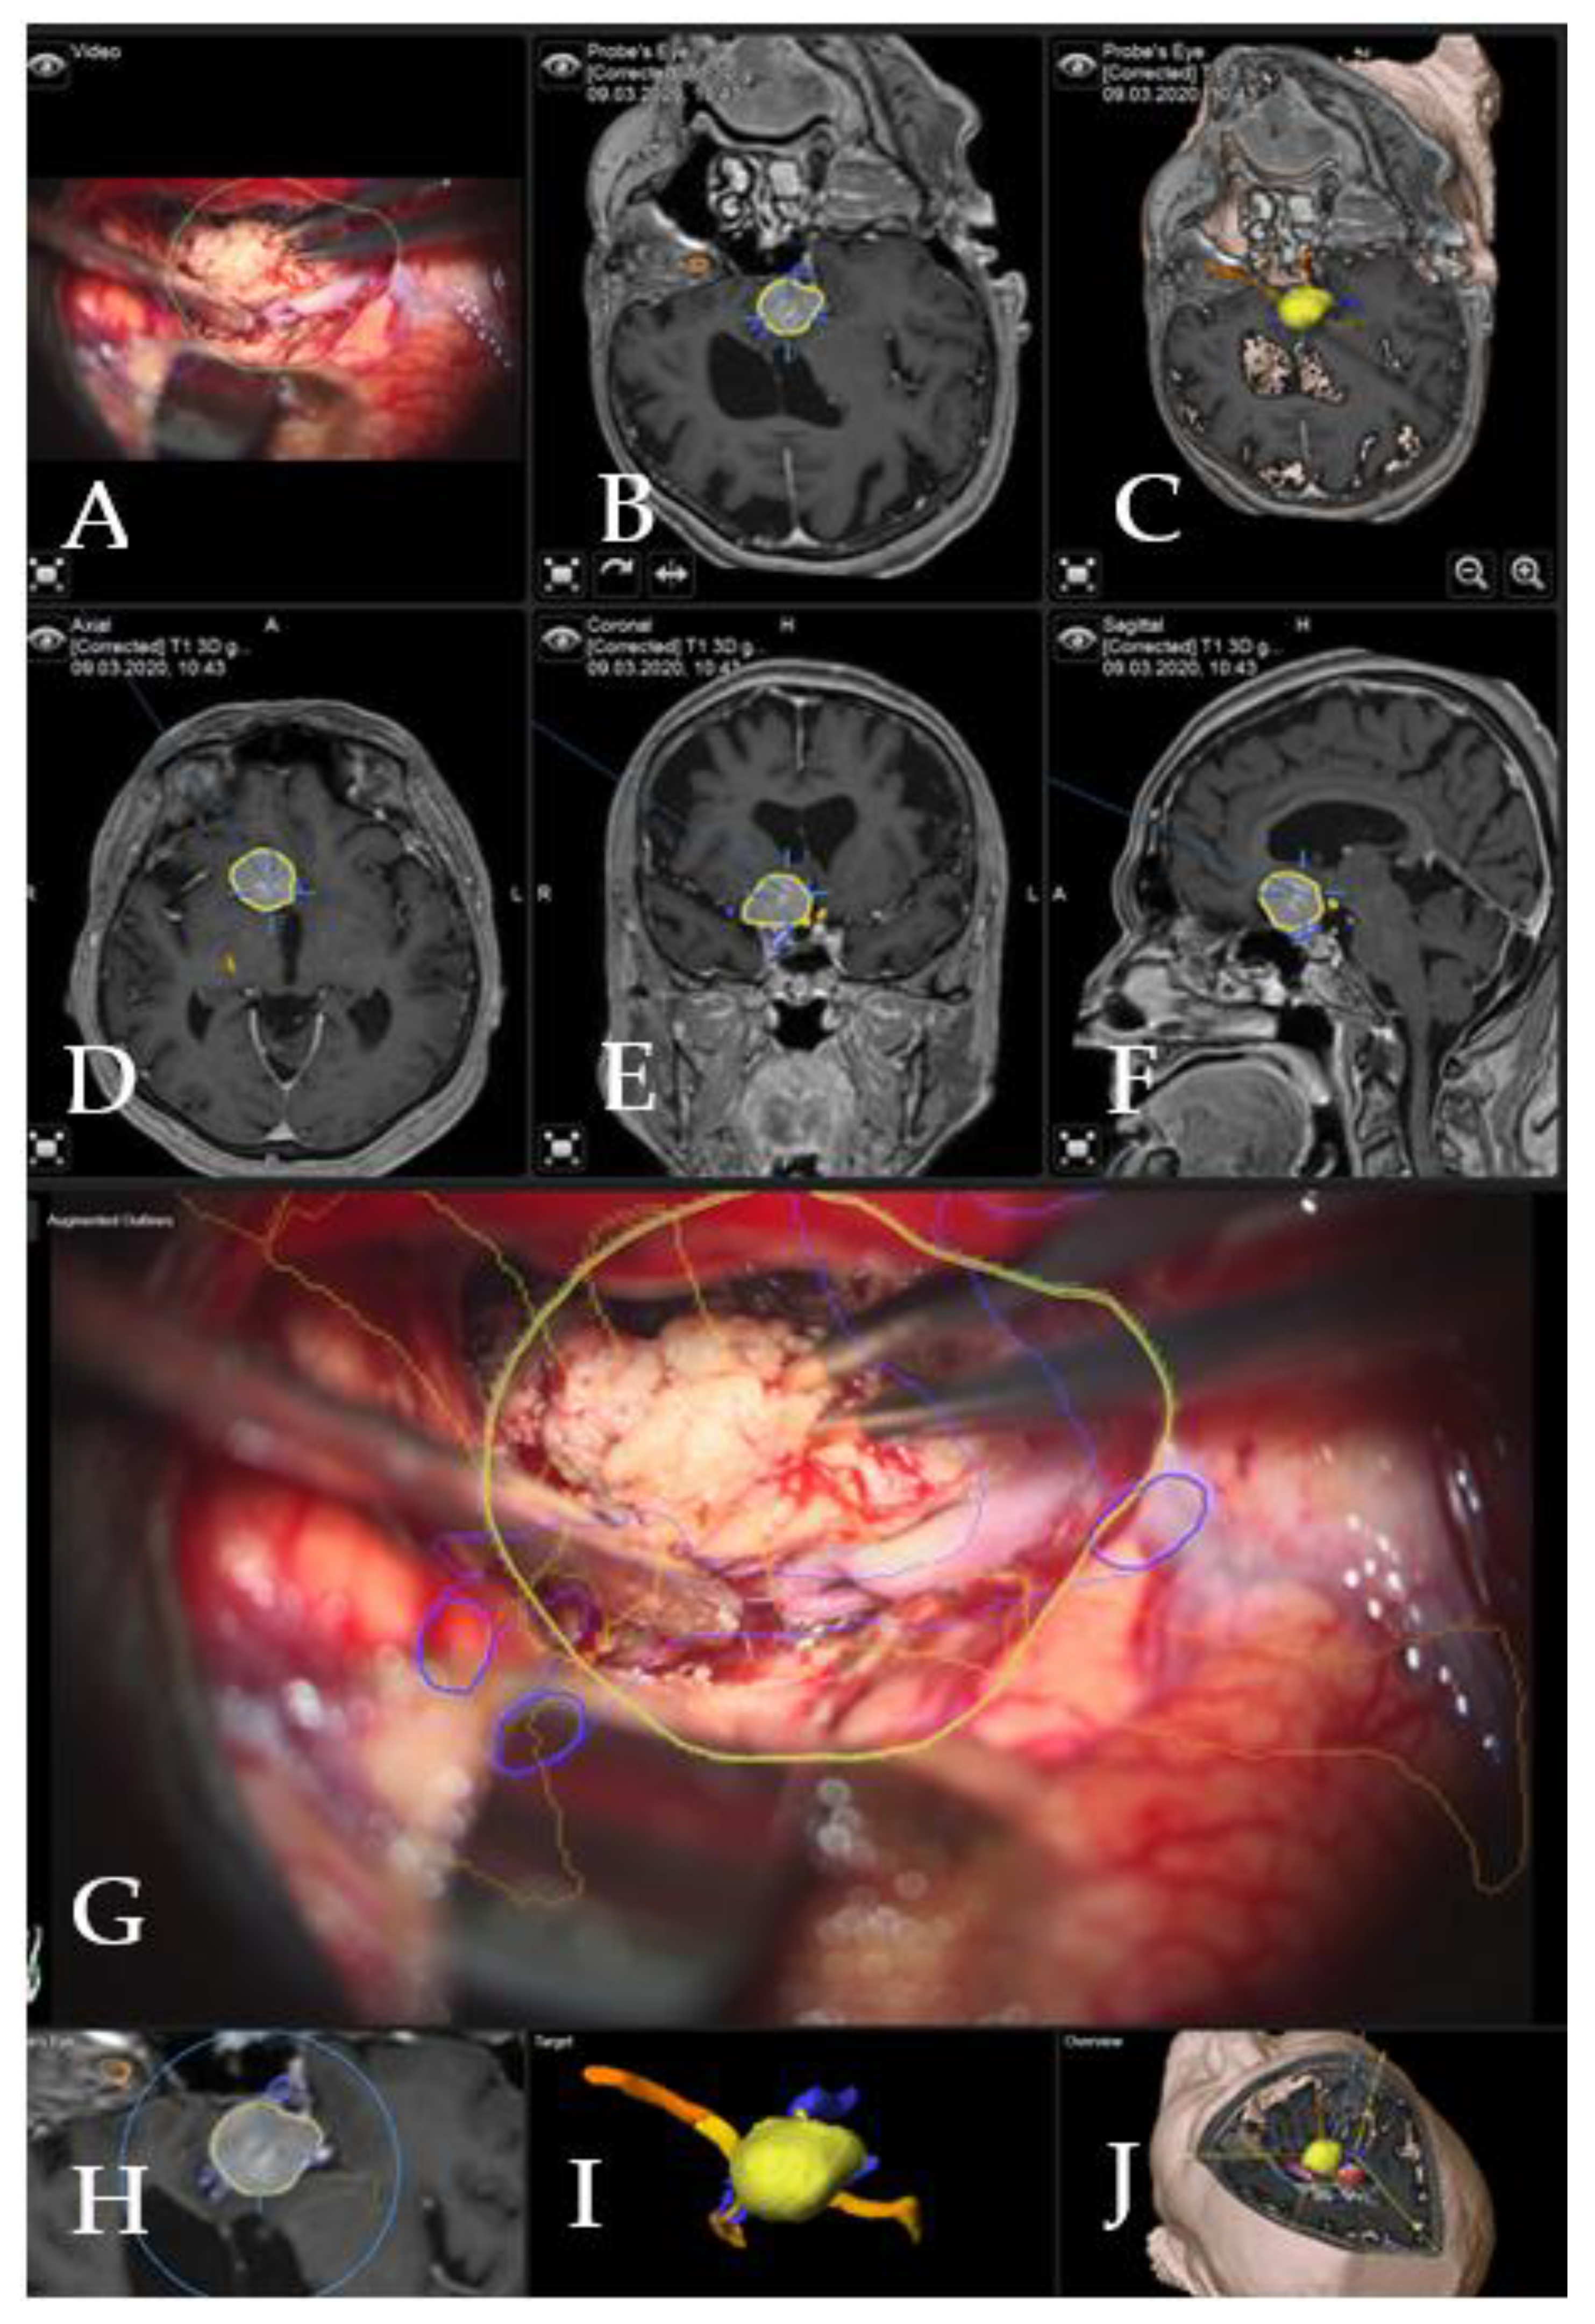

Augmented reality: The major indications to select a patient for surgery using the AR application were invasive tumors with encasement of the carotid and medial cerebral arteries, all tumors with close relation to the optic chiasm, giant tumors (tumor volume > 10 cm3) or recurrent tumors. Accuracy of patient registration and microscope registration were the two dependent variables for clinical AR accuracy. Microscope registration accuracy was checked by applying the AR visualization of the reference array outline. Landmark checks were successfully performed, apart from checking the target registration error (TRE), which confirmed high accuracy and excluded errors due to potential shift (Figure 2).

Figure 2. AR accuracy check. Patient no. 21 underwent a resection for suprasellar meningioma via right pterional approach. (A) Microscope video with focus on the tumor following exposure, with (A1) T1-weighted post-contrast MRI axial view of standard navigation display with segmented objects (tumor, optic chiasm and nerves in yellow and carotid arteries in violet). Focus of the microscope is shown as seen on the standard navigation display. (B) Microscope video with head-up display and 3-dimensional (3D) visualization of the segmented objects during the resection, with focus on right optic nerve, which shows high accuracy with the intraoperative situation. (B1) T1-weighted post-contrast MRI axial view of navigation, with focus on right optic nerve. (C) Microscope video with head-up display and 3D visualization of tumor outline, optic nerve and ipsilateral carotid artery following tumor resection with focus on the skull base with (C1) T1-weighted post-contrast MRI axial view of navigation. (D) Same as in C, microscope focus is on the contralateral carotid artery; segmented tumor outline and the course of the contralateral optic nerve are visualized with (D1) T1-weighted post-contrast MRI axial view of navigation, which shows focus of the microscope as seen on the standard navigation screen.